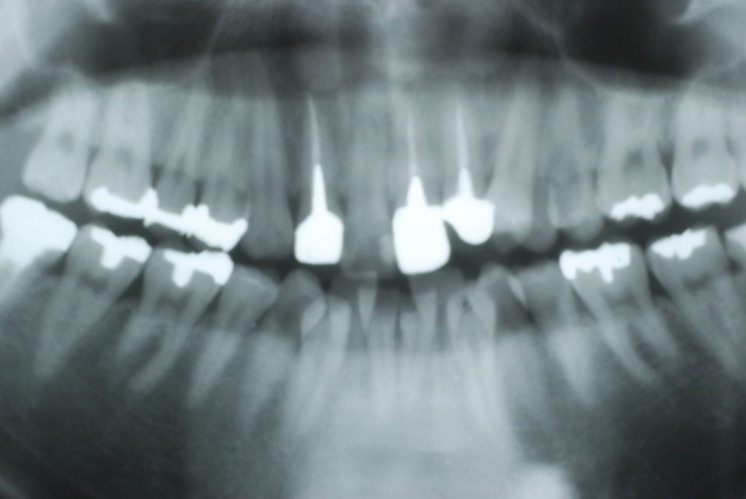

歯周病の疑いで東京のかなり遠方の方が来院されました。

驚くべきことですが、定期検診は受けていたそうです。しかしながら歯周病の指摘は受けたことがないそうです。

何故か?定期検診が虫歯のチェックのみになり、又肝心の歯周病の検査や歯周病の部分の予防や治療のためのブラシの使い方などを学んだ事がないのです。

本当に患者さんのことを考えると憂鬱になります。歯周病が悪化すると殆ど回復は無理だからです。